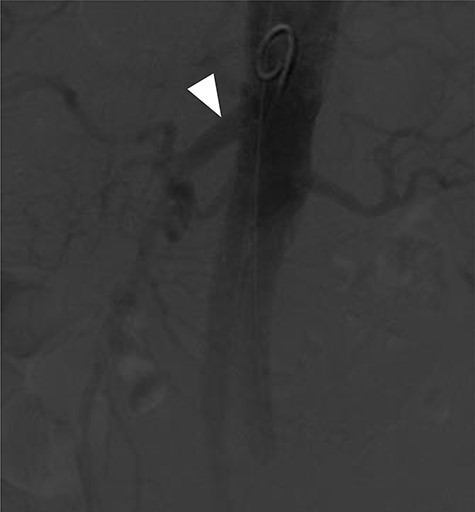

Although this was a planned elective FEVAR, several complications requiring two laparotomies, multi-organ dysfunction as well as patient’s multiple comorbidities contributed to prolonged intensive care unit (ICU) stay and delayed discharge. However, a multidisciplinary approach involving relevant specialties had allowed him to make a good recovery for rehabilitation and discharge home. Surveillance CT aorta at 1 month and 6 months post FEVAR showed satisfactory FEVAR appearance with no endoleak (Fig. 5).

Follow-up CTA showing all visceral stents patent and RRHA (arrow) from SMA (arrowhead).